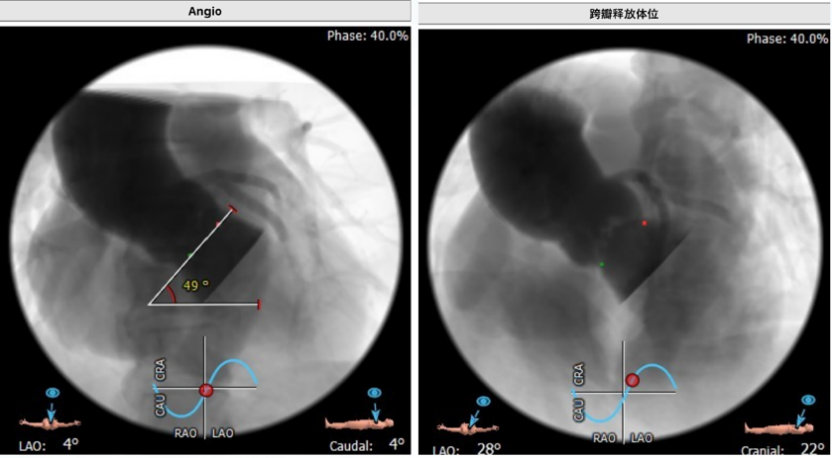

CT测算的造影和释放体位

手术策略

结合该患者的超声和CT分析,双侧股动脉直径可,手术团队选择右侧股动脉作为主要入路;同时考虑到患者为三叶瓣,左冠瓣叶钙化明显,冠脉开口高度可,开口处未见瓣叶。傅国胜教授团队也决定先采用22mm球囊预扩,而后植入一枚VitaFlow TAV 24型号瓣膜。